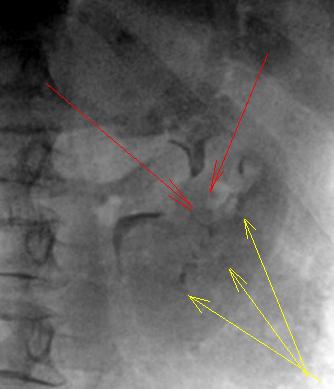

Однозначно наличествует патология со стороны левой почки. Об этом свидетельствует отсутствие контрастирования лоханки (красные стрелки), а также отсутствие контрастирования чашечек среднего и нижнего бокалов (желтые стрелки). На месте чашечек бесформенные "лужицы" контрастного вещества, что прямо указывает на нарушение структуры. Нельзя не отметить некоторую эктазию верхней большой чашечки с "ампутацией" шейки.

Тугого контрастирования почечной лоханки также не наблюдается, не контрастированы малые чашечки группы среднего бокала.

По всей видимости, можно предположить наличие двустороннего воспалительного процесса лоханок.